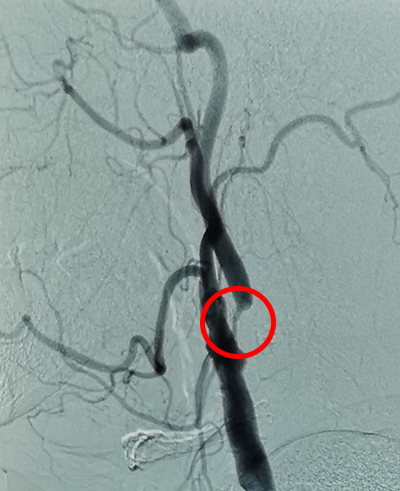

刘女士的造影

? 右侧颈内动脉重度狭窄(70~99%)

? 短暂性脑缺血发作